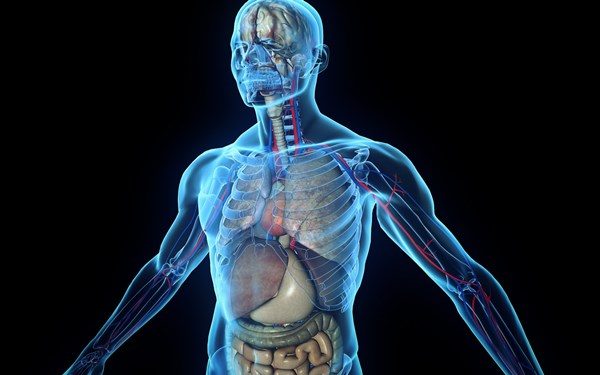

Não é bem uma descoberta ou uma criação. O mesentério já existia, mas como uma membrana que faz parte do sistema digestivo e liga os intestinos ao abdómen. Agora é que passou a ser considerado um único órgão contínuo.

“A descrição anatómica que foi feita nos últimos 100 anos de anatomia estava incorreta. Este órgão está longe de ser fragmentado e complexo. É simplesmente uma estrutura contínua”, explicou J. Calvin Coffey, investigador da universidade do hospital irlandês de Limerick.

Os cientistas pretendem agora compreender a função do novo órgão, além de proporcionar sustentação e permitir a irrigação sanguínea. Com esta reclassificação, espera-se que o mesentério possa ajudar no tratamento de doenças abdominais e digestivas, com menos cirurgias invasivas e menos complicações na recuperação dos doentes.